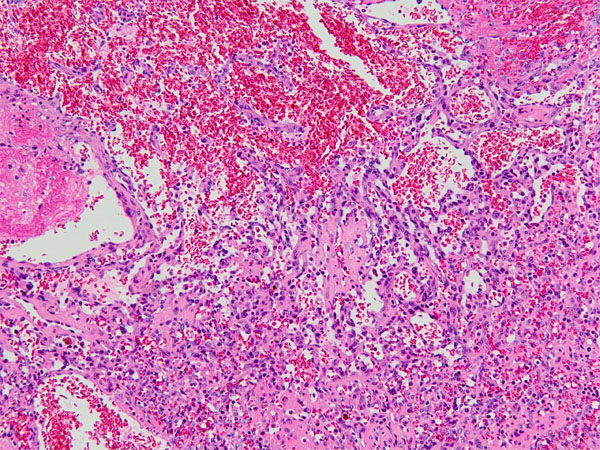

ワンちゃんが乳腺にできた複数のシコリを気にされて来院されました。bilateral mastectomyで対応しました。摘出後の病理組織検査の結果は、「R3-4間腫瘤:乳腺癌(複合型)」でそれ以外は「良性乳腺混合腫瘍」でした。無事元気に退院し、その後再発もなく経過は良好です。よかったね。